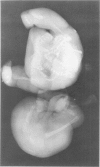

Fetus-in-fetu is an unusual cause of retroperitoneal abdominal mass in infants, which most likely arises from inclusion of a monozygotic, diamniotic twin. This entity is distinguished from teratoma by its embryological origin, its unusual location in the retroperitoneal space, its invariable benignity, and by the presence of vertebral organization with limb buds and well-developed organ systems. Diagnosis is made radiographically by the finding of a diminutive vertebral column on a plain abdominal film. The treatment of choice is total excision with special attention being given to the fetus' blood supply which may be directly from the host's superior mesenteric vessels. A well-documented example of this unusual entity that occurred in a six-week old infant male is presented.